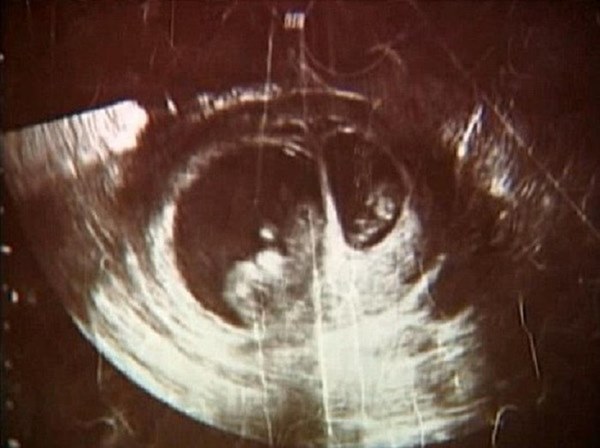

Chính xác. Siêu âm rất có thể bị nhầm lẫn giữa siêu thai và mang thai đôi vì đều thấy có hai em bé trong tử cung người mẹ. Nhưng sẽ có sự khác biệt về tuổi thai với việc mang thai đôi, bởi vì hai đứa trẻ được thụ thai ở hai thời điểm khác nhau (ngay cả khi cách nhau vài ngày hoặc vài tuần).

Theo nghiên cứu, có thể có khoảng cách đáng kể về kích thước của hai thai nhi, nhưng điều này cũng phổ biến ở các cặp song sinh thông thường khi hai bé cần nhiều dinh dưỡng hơn so với các trường hợp thai đơn. Sinh đôi cũng có thể phát triển ở các giai đoạn khác nhau.